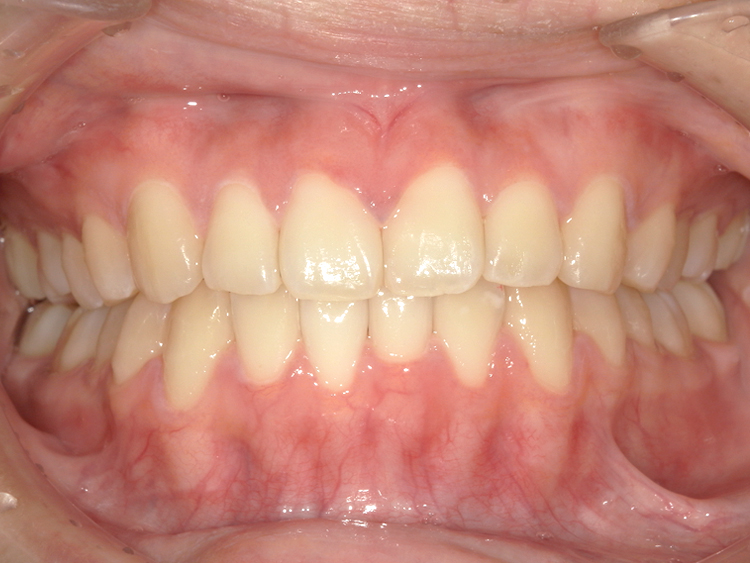

症例5

Before

After

| 主訴 | 上下3-3の並びが気になる |

| 年齢 | --- |

| 治療 期間 |

約1年 |

| 治療 内容 |

インビザライン5-5 |

| 治療費 | ¥517,000(税込)/調整料含む |

| 治療のリスク | 奥歯を動かさないので、前に出して並べていく。 歯と歯が移動するスペースを作るので、知覚過敏の症状がまれにでる。 歯を動かすことで、歯茎が下がるリスクある。 矯正終了後は、リテーナーを使用し、後戻りを防ぐ必要がある。 |